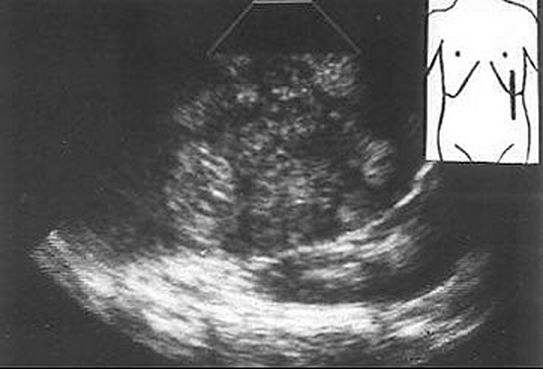

El bazo normal se presenta en la ecografía como una estructura triangular situada en el hipocondrio izquierdo con un patrón ecogénico homogéneo y una ecogenicidad igual o inferior a la del hígado.

Existen varias formas para determinar ecográficamente la esplenomegalia. Por su sencillez, la más utilizada es la medición del eje longitudinal que, en general, es igual o inferior a 11 cm, considerándose anormal o aumentado cuando es superior a 12-13 cm. El diagnóstico diferencial de una esplenomegalia es difícil y la ecografía no suele constituir una ayuda en el establecimiento de su etiología. Se realiza con el paciente en decúbito supino, realizándose cortes subcostales, longitudinales y transversales, desde epigastrio hasta hipocondrio derecho.